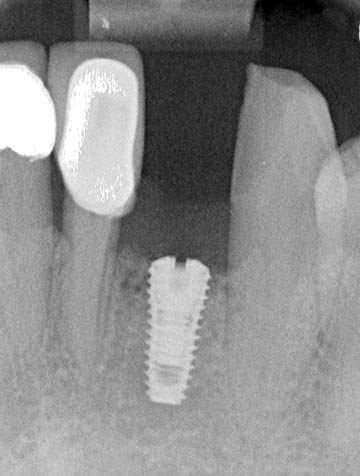

This gentleman had lost his heavily restored UL4 and decided to close the space with an implant retained crown. The thin buck-palatal width required careful placement to avoid fenestration bucally. A tooth bourn position guide was used to place the implant predictably and within the aesthetic envelope. The implant was restored after three months of osseointegration with a bonded crown.